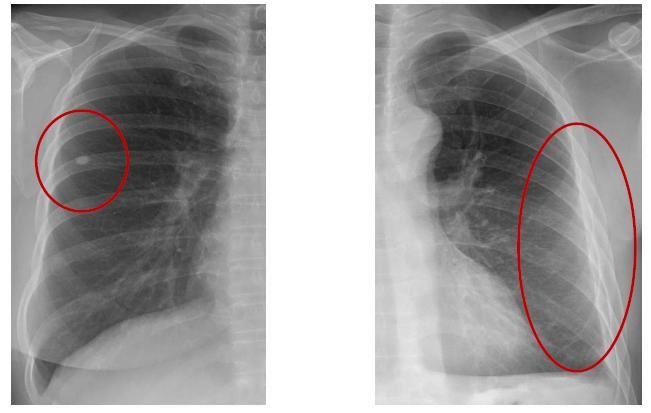

건강검진 엑스레이찍었는데 이런 비슷한 결절이 나왔어요 꼭 봐주세요

올해 만 40세로 국가 건강검진 받았는데 엑스레이를 찍었더니 사진과 비슷한형태의 결절이 있다고 폐시티 찍자해서 찍고 일주일뒤 결과보러가기로했는데요 너무 걱정되서요 사진은 제사진은 아니고 인터넷에 보니 저랑 비슷한사진은 저것뿐이라서요

모양도 비슷하고 크기도 비슷하고 투명하다기 보다

저렇게 밝은 형태를 뛰고 있습니다

왼쪽사진입니딘

결절은 매우 흔하게 발견됩니다,, 결국은 암인지 아닌지가 중요한데, 보통 6mm ~ 8mm 정도 결절이라면 암일 확률이 1~2% 정도 된다고 합니다. 일단 CT 결과 확인해봐야겠지만,, 결절로 오는 분들 대부분은 크기가 작아서 경과관찰 하기는 합니다.

단지 모양 그러니까 margin이 이처럼 뚜렷하고 색도 균일하고 하는 경우에는 악성의 가능성이

높지는 않습니다.